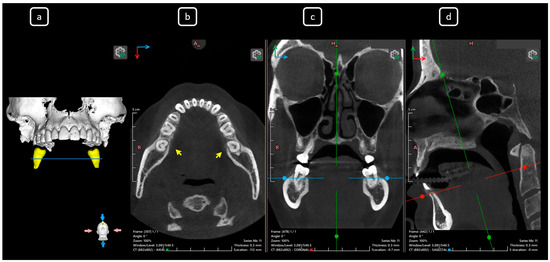

Cone beam computed tomography (CBCT) is a valuable diagnostic tool for evaluating the upper airway and maxillofacial region. This report demonstrates the clinical value of CBCT in identifying significant anatomical variations in endodontics, incidentally detected on a non-endodontic CBCT scan. A 23-year-old female patient underwent CBCT imaging at the Faculty of Dentistry-UJED to evaluate her upper airway. CBCT imaging revealed a unique, complex, and unusual anatomy of mandibular root canals, characterized by Vertucci’s type III root canals in the anterior sextant and co-occurrence of bilateral C-shaped mandibular second molars (type C2 according to Fan’s classification). No therapeutic interventions were initiated due to the patient’s asymptomatic status. CBCT imaging is a valuable tool for integrated diagnostic approaches, underscoring its role in thorough patient management. The integration of multidisciplinary interpretation of CBCT data can enhance diagnostic accuracy and optimize patient records and management, emphasizing the importance of collaborative efforts between radiologists, clinicians, and endodontists. Documenting and sharing such findings can increase awareness of rare anatomical variations, facilitating detection and contributing to medical knowledge. Full article

Figure 1